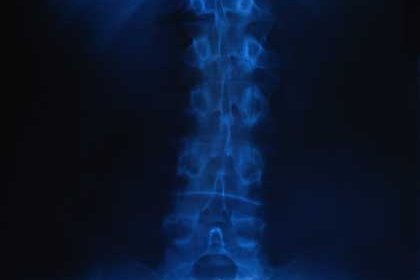

Etwa 2% der 10- bis 16-Jährigen in Deutschland sind von einer Skoliose betroffen. Bei einer Skoliose entwickelt sich z.B. eine seitliche Krümmung der Wirbelsäule. Sie entsteht, wenn sich einzelne Wirbelkörper um ihre eigene Achse verdrehen. Dort sind die Wirbel dann versteift. Auch Verbiegungen nach vorn (Kyphose) und nach hinten (Lordose) können auftreten. Genetische Faktoren spielen anscheinend eine entscheidende Rolle dabei. Jeder siebte junge Mensch mit Skoliose hat eine so starke Krümmung, dass sie behandelt werden muss.